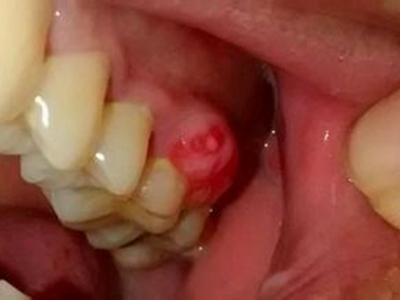

牙龈瘤多发于女性,以青年及中年人为常见,多发生于牙龈乳头部,位于唇、颊侧者较舌、腭侧者多,最常见的部位是前磨牙区。肿块较局限,呈圆形或椭圆形,有时呈分叶状,大小不一,直径由几毫米至数厘米。

肿块有的有蒂,如息肉状;有的无蒂,基底宽广,生长较慢,但在女性妊娠期间可能迅速增大。较大的肿块可以遮盖一部分牙及牙槽突,表面可见牙压痕,易被咬伤而发生溃疡,伴发感染。随着肿块的增长,牙槽骨壁逐渐被破坏,牙可能发生松动、移位。

对于牙龈瘤可在局麻下手术切除,切除必须彻底,否则易复发。如果复发,仍可手术切除。多次复发者,即使病变波及的牙无松动,也应将牙拔除,防止再发。